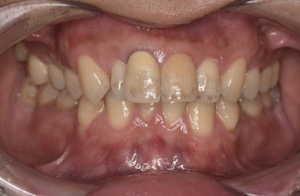

CASE 2

Before

After

基本情報

| 年齢・性別 | 30代・男性 |

| 主訴 | 歯石を取りたい |

| 治療内容 | 超音波スケーラーでの歯石除去 |

| 治療期間 | 60分 |

| 治療費 | 初診料を含め約4,500円 |

| リスク・副作用 | 歯ぐきに違和感や痛みを覚える場合がある。 1週間程度、歯を磨くといつもより出血することがある。 腫れていた歯ぐきが引き締まることで歯ぐきが下がった様に見える。 歯ぐきが下がることで歯がみしやすくなることがある。 一時的に歯の動揺(ゆれ)が増す場合がある。 |